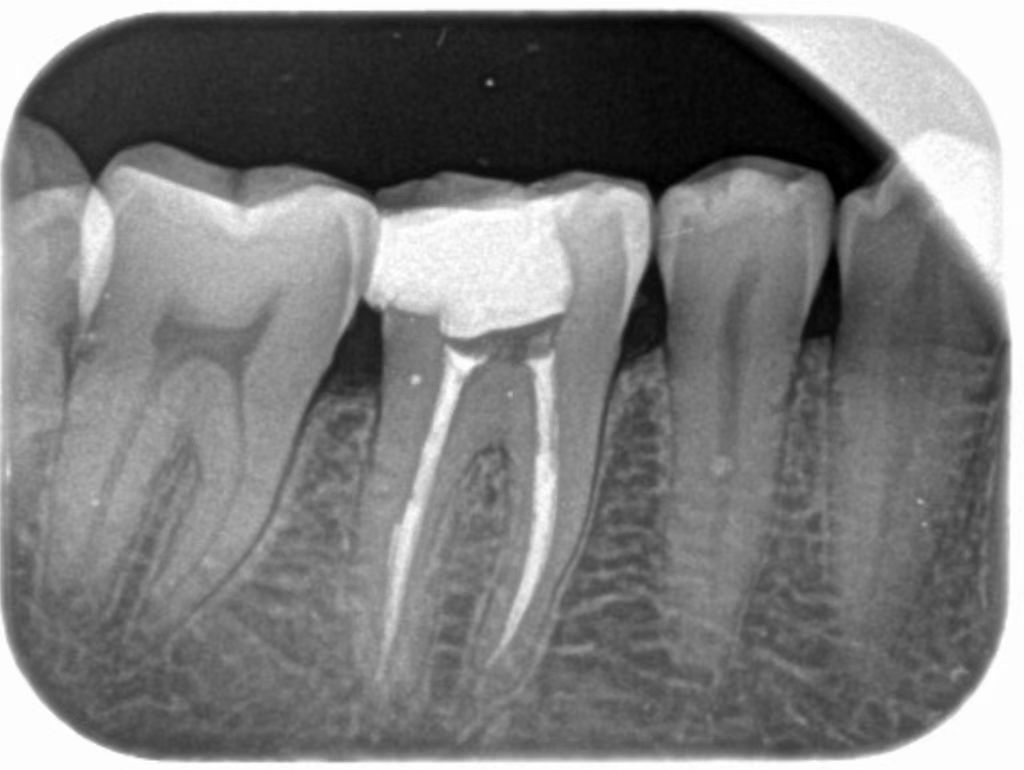

1、比较常见的就是龋齿造成的牙齿缺损、牙髓炎症等等情况的补牙。如果龋洞比较浅,龋齿仅仅波及到牙齿的釉质层或者进一步发展波及到牙本质层都可以进行保守性的补牙治疗。如果龋齿波及到了牙髓引起了牙髓的炎症、根尖的炎症就需要进行根管治疗再补牙。